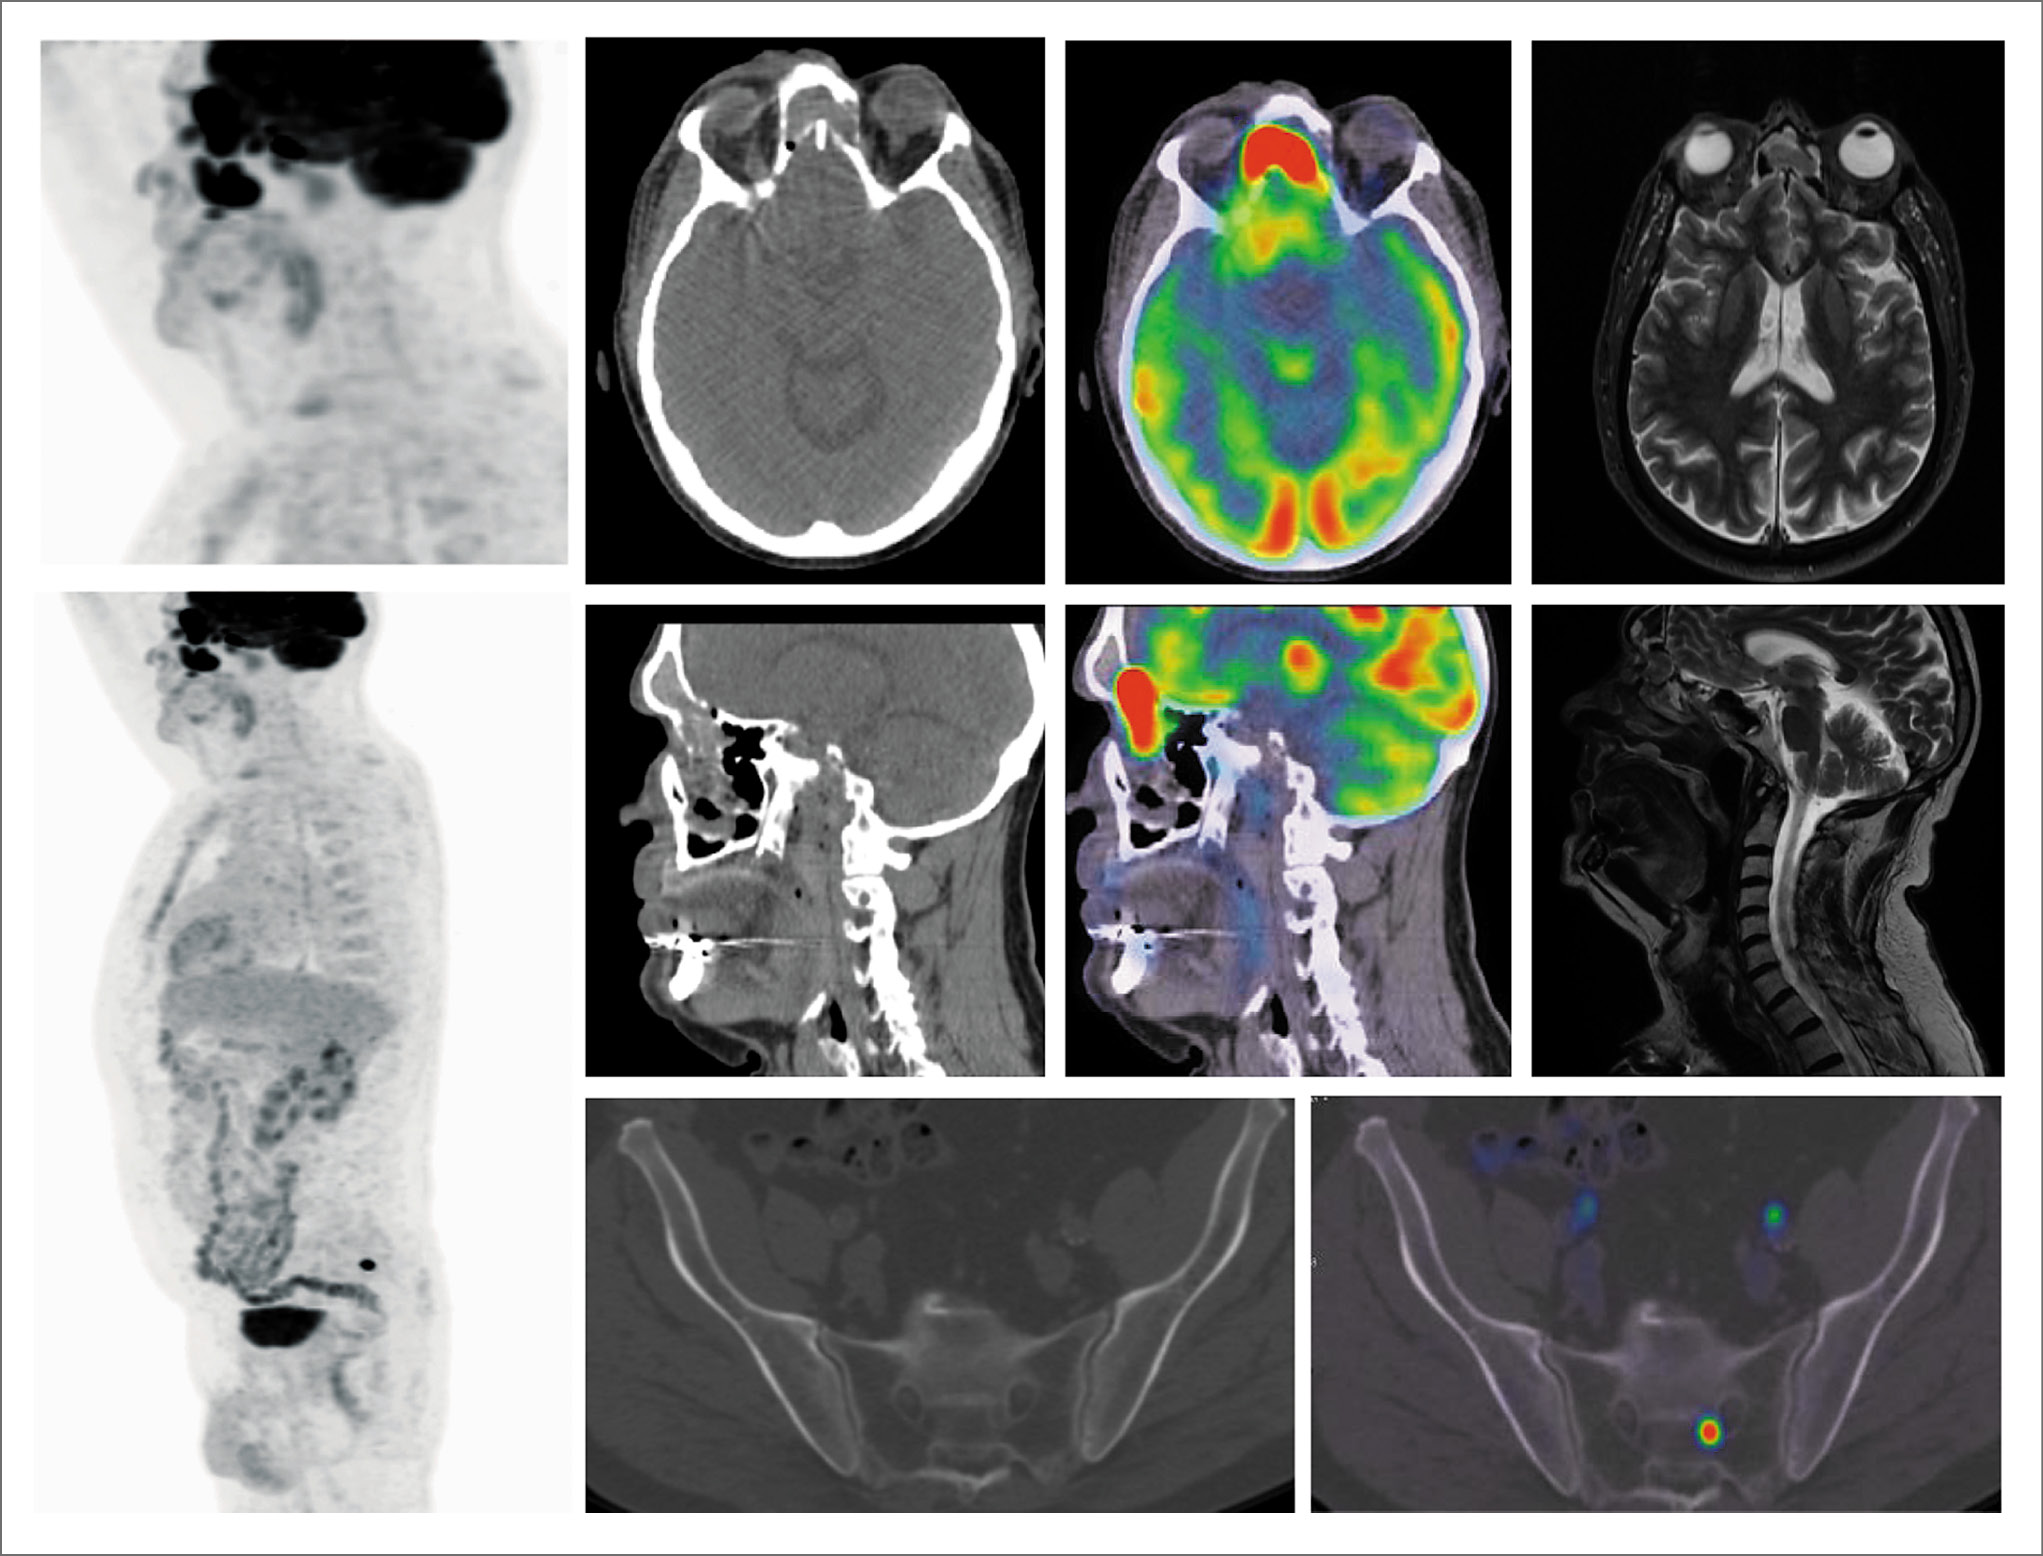

Произведена ПЭТ/КТ с 18F-фтордезоксиглюкозой. На фоне неравномерно утолщенной слизистой оболочки клеток решетчатого лабиринта, носовых раковин, верхнечелюстных и лобной пазух определяются гиперметаболические участки размером до 22×13 мм, SUVmax 19,1 – наибольший в области решетчатой пазухи и левой нижней носовой раковины с переходом на левую гайморову пазуху. Дополнительно в левой боковой массе крестца S2 определяется очаг повышенной фиксации радиофармпрепарата (РФП) без структурных изменений размером 15 мм, SUVmax 19,6 (рис. 1).

Рис. 1. Пациент Т., 63 года. На MIP ПЭТ, аксиальной, сагиттальной КТ и совмещенных ПЭТ/КТ проекциях на фоне неравномерно утолщенной слизистой оболочки клеток решетчатого лабиринта носовых раковин, верхнечелюстных и лобной пазух определяются гиперметаболические участки с повышенным накоплением РФП, SUVmax 19,1. В левой боковой массе крестца SII имеется очаг повышенной фиксации РФП без структурных изменений, SUVmax 19,6.

Установлен диагноз: эстезионейробластома T2N0M1, стадия D по Kadish. Метастазы в кости. С учетом распространенности опухолевого процесса назначена лучевая терапия на первичную опухоль с последующей полихимиотерапией.